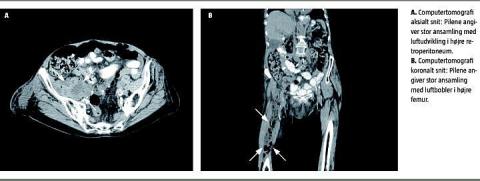

Pga. stigende infektionstal og usikkert infektionsfocus blev der foretaget UL af abdomen og femur, og man fandt en fladeformet ansamling med luftindhold udgående fra bløddelene i bækkenet. En efterfølgende computertomografi af abdomen uden brug af intravenøs kontrast bekræftede sænkningsabsces, der strakte sig fra højre musculus iliopsoas til knæledsniveau.